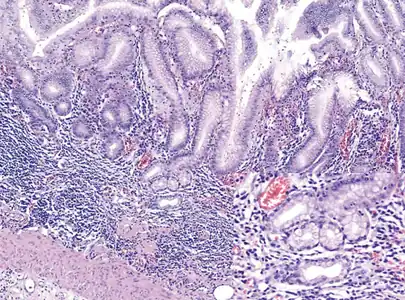

Atrophic gastritis under low power. H&E stain.

Autoimmune metaplastic atrophic gastritis (AMAG) is an inherited form of atrophic gastritis characterized by an immune response directed toward parietal cells and intrinsic factor.[6] The presence of serum antibodies to parietal cells and to intrinsic factor are characteristic findings. The autoimmune response subsequently leads to the destruction of parietal cells, which leads to profound Achlorhydria (and elevated gastrin levels). The inadequate production of intrinsic factor also leads to vitamin B12 malabsorption and pernicious anemia. AMAG is typically confined to the gastric body and fundus.

Achlorhydria induces G cell (gastrin-producing) hyperplasia, which leads to hypergastrinemia. Gastrin exerts a trophic effect on enterochromaffin-like cells (ECL cells are responsible for histamine secretion) and is hypothesized to be one mechanism to explain the malignant transformation of ECL cells into carcinoid tumors in AMAG.